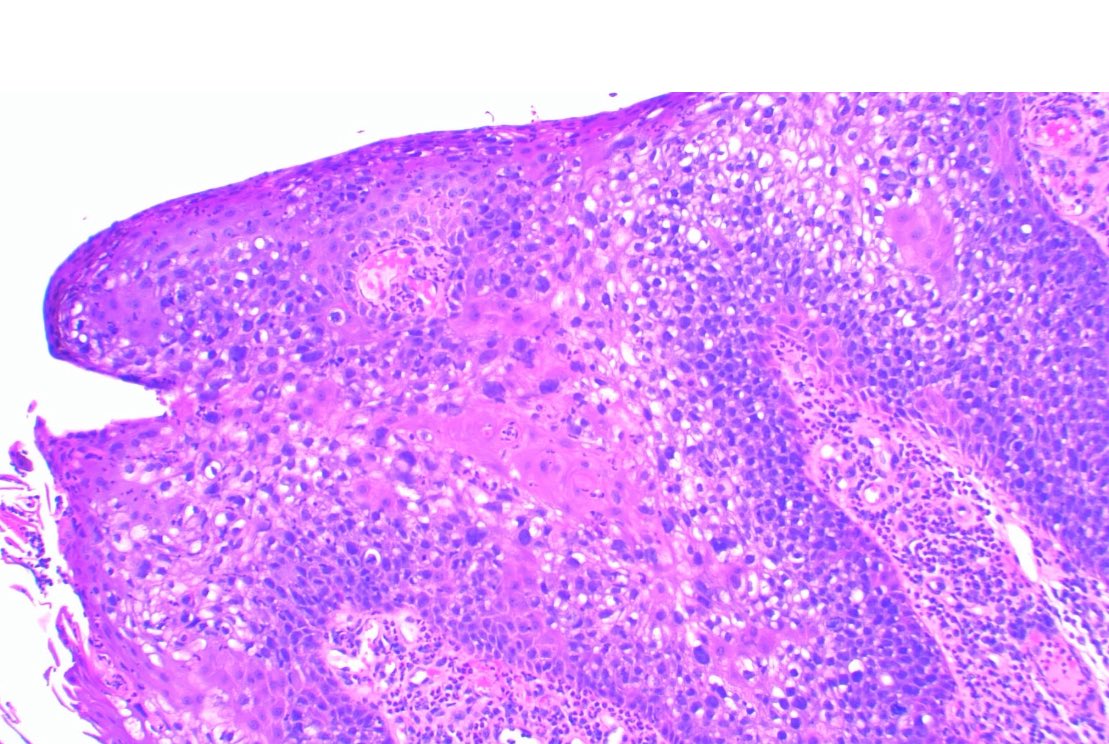

Beautiful tangential cut appearance of verucous carcinoma featuring rounded retes pegs. #pathology #dermpath #verrucous_carcinoma